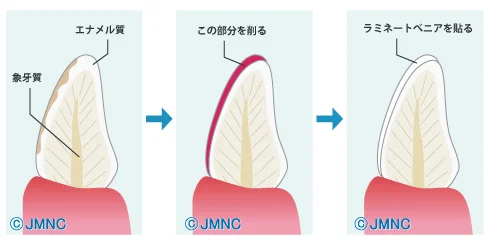

前歯のダイレクトベニア

こんにちは。 最近紹介での初診が非常に増えています。 元々看板なども出していないため、知り合いからの紹介が多かったのですが、どんどん増えてきています。 現在初診で来院される方の約9割がどなたかからの紹介となっていますので、私の治療に満足して…

続きを読む →